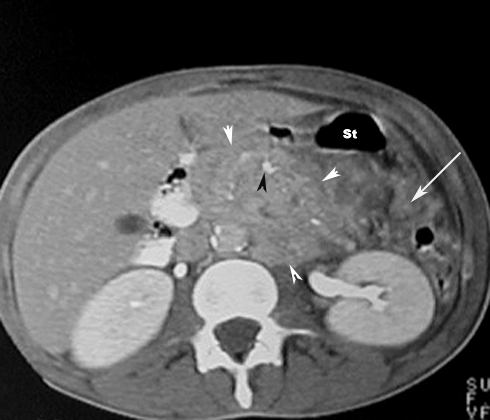

CT scan in Acute Pancreatitis

Phlegmon / Inflammatory mass

• White arrowheads: Phlegmon

• Black arrowhead:   Pancreatic calcification

• Large Arrow: Peripancreatic fascial infiltration

St: Stomach